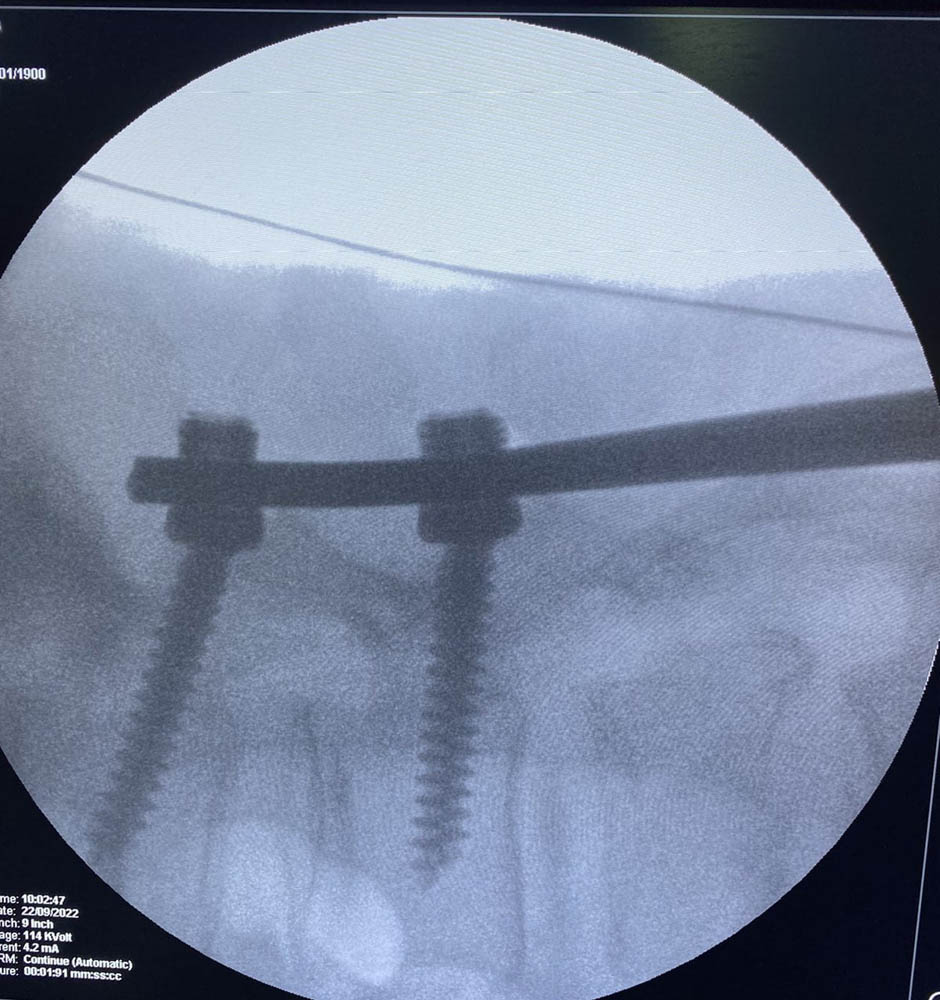

За інформацією Охтирської міськради, співпраця розпочалася із проведення операцій на хребті найсучаснішим методом. Завідувач відділенням ортопедії та травматології Університетської клініки д-р. мед наук Дмитро Петренко спільно з лікарем відділення Дмитром Демченком вже провели в Охтирці дві операції на хребті. У одного пацієнта була травма, у іншого – грижа хребта. Оперативні втручання пройшли успішно і без ускладнень.

«Хірургія хребта – це дуже складна частина ортопедії та травматології, на підготовку таких фахівців потрібно багато часу і зусиль, а працюють вони виключно в спеціалізованих центрах в Києві та Харкові. Для невеличких міст – це мрія! Нам же вдалося започаткувати та вже провести такі складні операції в Охтирці завдяки вдалій співпраці адміністрацій Університетської клініки, Охтирської лікарні та за дієвого сприяння Охтирської міської ради, – розповідає Дмитро Петренко. – Умови в Охтирській лікарні та кваліфікація місцевих лікарів дозволяє впевнено і спокійно робити такі операції на постійній основі. Хочемо подякувати колегам, які запросили нас до себе, ми обов’язково будемо продовжувати розвивати регіональну медицину, що є сучасним трендом реформування медичної галузі України».